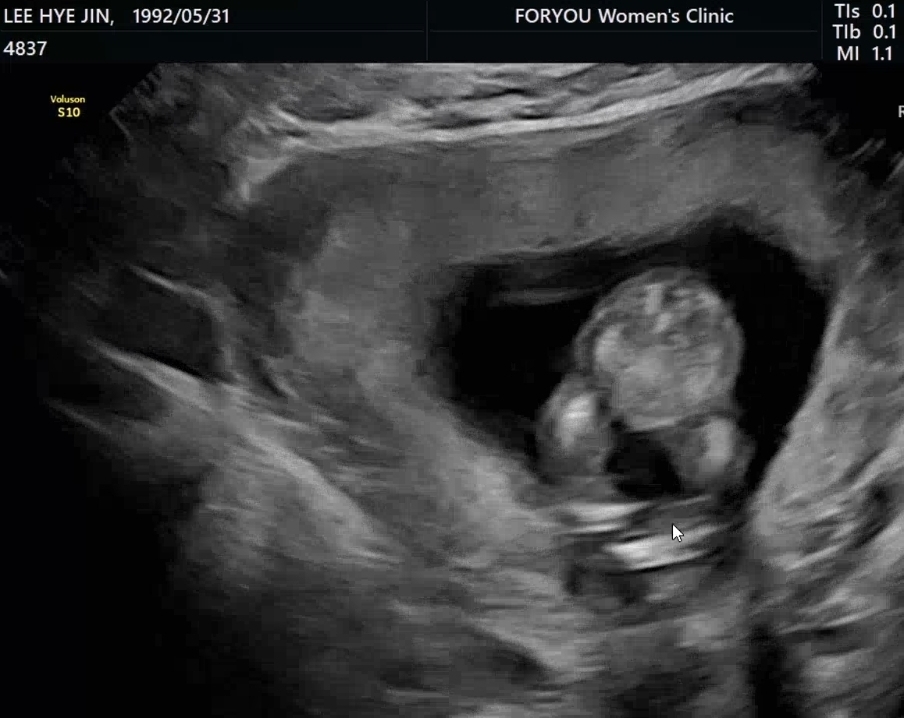

14주6일차 성별확인

초음파 보고왔는데 이정도면 딸 확정일까요?🤔

오! 이 정도면 확정일꺼같은데용???ㅎㅎ